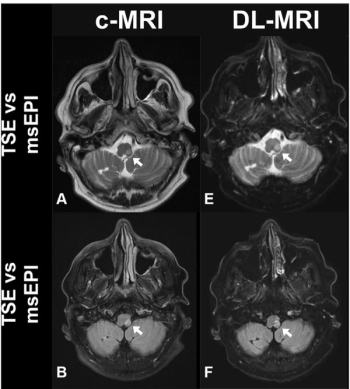

For patients with suspected acute stroke, researchers noted higher image quality for deep learning-accelerated MRI, which can be completed over 11 minutes sooner than similar sequences for conventional MRI.